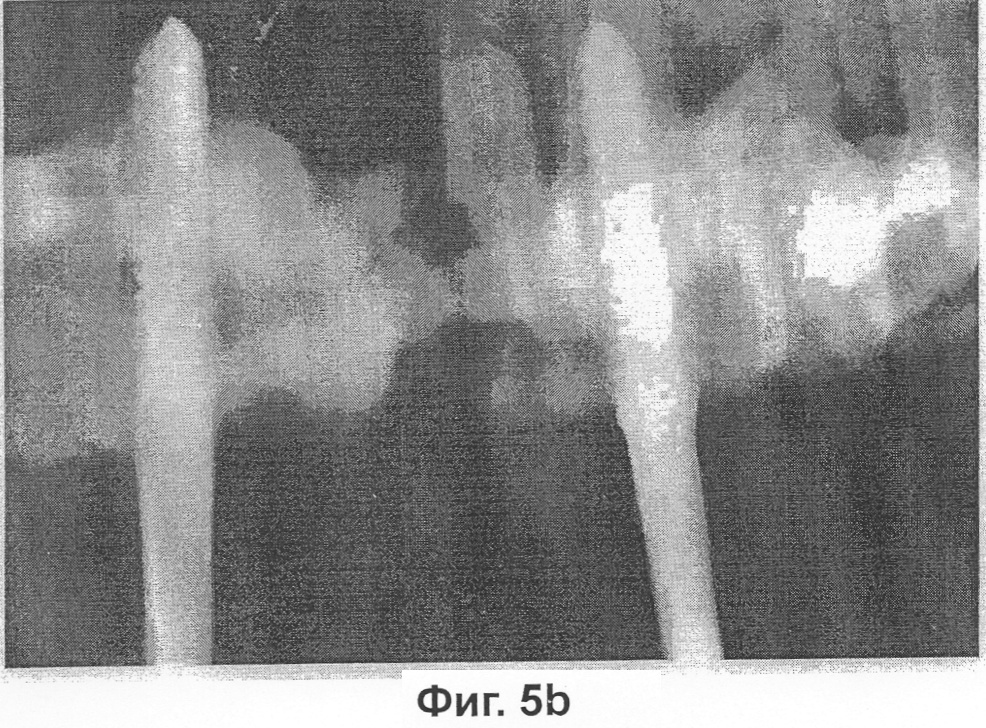

Фиг.5B представляет собой фотографию, на которой показана степень сращения кости в получавшей сульфат кальция группе 2, которую оценивали по методу рентгенографического исследования через 6 недель после вытяжения кости, конкретно животным, получавшим сульфат кальция группы 2, инъецировали композицию по настоящему изобретению и индуцировали вытяжение на 2 мм в сутки в течение 5 суток.

В результате в каждой группе, в которой проводилось вытяжение кости на 2 мм в сутки, за исключением контрольной группы, наблюдалась кальцификация вокруг участка вытяжения челюстной кости, что подтверждалось рентгенограммами, полученными на 3 неделе и на 6 неделе после вытяжения. Между разрезанными частями челюстной кости также наблюдалась рентгенопрозрачная зона, а примыкающие с обеих сторон к разрезанным частям челюстной кости участки соединения различались от группы к группе. На 3 неделю после вытяжения кости в контрольной группе, в которой проводилось вытяжение кости на 1 мм или на 2 мм в сутки без инъекции композиции по настоящему изобретению, как и в другой группе, в которой проводилось вытяжение кости на 2 мм в сутки с инъекцией композиции, рентгенопрозрачная зона была едва различима, тогда как в группе, в которой проводилось вытяжение кости на 1 мм в сутки с инъекцией композиции, наблюдалась массивная рентгеноконтрастная зона. На 6 неделю после вытяжения кости рентгеноконтрастная зона значительно распространилась по направлению к центру участка вытяжения как в контрольной группе, в которой проводилось вытяжение кости на 1 мм в сутки без инъекции композиции по настоящему изобретению, так и в группе, в которой проводилось вытяжение кости на 1 мм или на 2 мм в сутки с инъекцией композиции. Наибольшая рентгеноконтрастная зона наблюдалась в группе, в которой проводилось вытяжение кости на 1 мм в сутки с инъекцией композиции по настоящему изобретению, тогда как в контрольной группе, в которой проводилось вытяжение кости на 2 мм в сутки без инъекции композиции по настоящему изобретению, рентгеноконтрастная зона была едва различима (см. фиг.3-5).

В результате в каждой группе, за исключением контрольной группы 2, в участке вытяжения челюстной кости наблюдалась кальцификация (фиг.3-5). Подтверждено образование рентгенопрозрачной зоны между разрезанными частями челюстной кости и примыкающих к разрезанным частям челюстной кости с обеих сторон участков соединения. На 3 неделю после вытяжения кости в контрольных группах и в получавшей композицию по настоящему изобретению группе 2 рентгенопрозрачная зона была едва различима, тогда как в получавшей композицию по настоящему изобретению группе 1 наблюдалась массивная рентгеноконтрастная зона. На 6 неделю после вытяжения кости в каждой группе, за исключением контрольной группы 2, рентгеноконтрастная зона значительно распространилась по направлению к центру участка вытяжения, а наибольшая рентгеноконтрастная зона наблюдалась в получавшей композицию по настоящему изобретению группе 1.